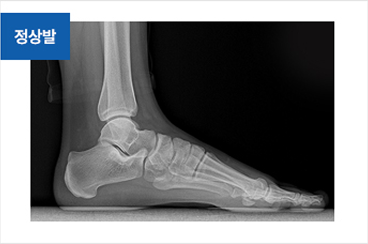

족저근막염

족저근막염 치료 전

족저근막염 치료 후

족저근막염이 생기는 원인

• 조깅, 등산, 마라톤, 축구 및 농구와 같은 구기종목을 과도하게 할 경우

• 딱딱한 바닥에서 장시간 서 있거나 반복적으로 점프할 때

• 체중이 급격히 증가할 경우

• 하이힐을 장시간 착용하고 보행할 경우